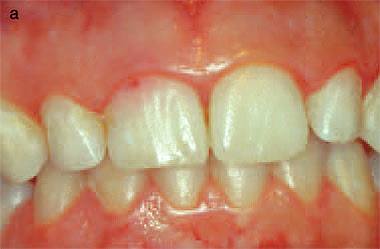

เคสนี้มองในปากทางด้าน palatal เห็นฟันสีออกแดงเรื่อๆ ขนาดนี้เลย ลักษณะกลไกป้องกันตัวเองของฟันจาก film x-ray (radiopaque line) เป็นข้อบ่งชี้ว่า ฟันซี่นี้กำลังเผชิญกับ active form ของ tooth resorption

film ของฟันหลัง ที่เจอ Invasive cervical resorption Class 2

ในคลินิก มองไม่เห็นความผิดปกติใดๆ (ไม่มี discoloration)